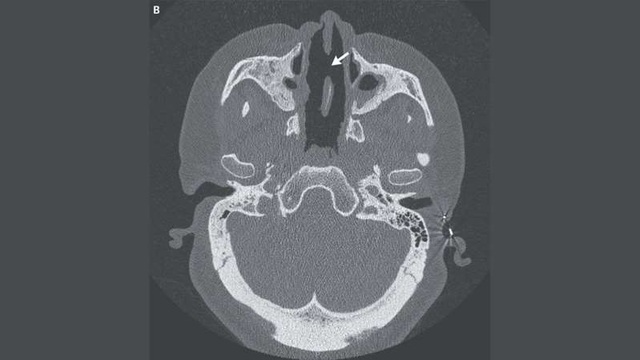

Ảnh chụp CT sọ mặt của người phụ nữ. Mũi tên chỉ vào một lỗ hổng lớn trên vách mũi.

Khám sức khỏe cho thấy xương mũi - nằm ở hai bên sống mũi - của người phụ nữ bị "mất gần như toàn bộ", và sụn vách ngăn mũi bị thoái hóa nghiêm trọng. Ngoài ra, chụp cắt lớp vi tính (CT) cho thấy một lỗ hổng lớn đã hình thành trong vách ngăn mũi.